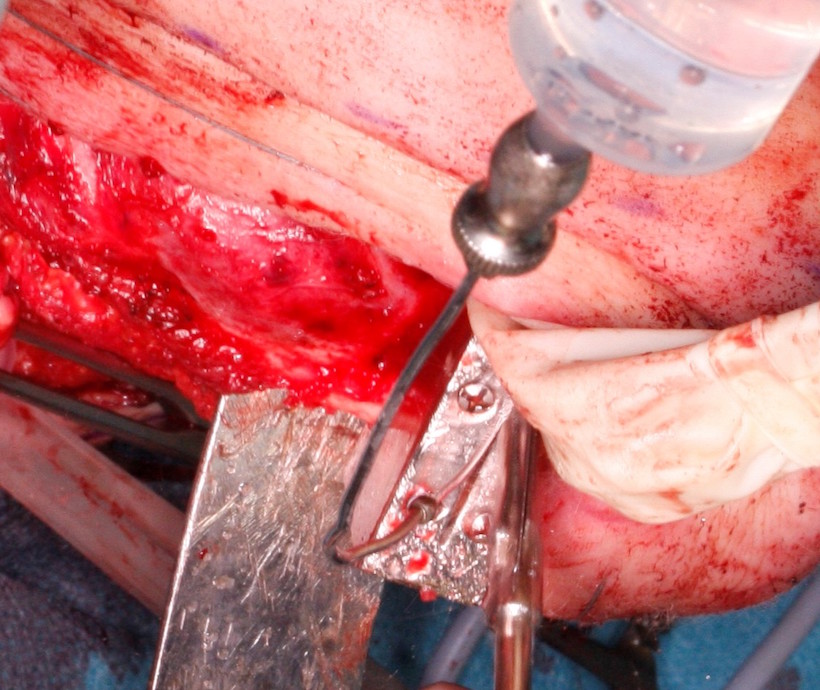

W dniu 19.05.2021 wykonano zabieg w znieczuleniu ogólnym. Z cięcia przedusznego Redona po stronie prawej oraz Shaha w środkowym fałdzie szyi pod kontrolą neuronawigacji odsłonięto sktruktury anatomiczne szyi. Wypreparowano i odcięto prawą tętnicę i żyłę twarzową do mikrozespoleń. Następnie odsłonięto trzon, kąt, gałąź i wyrostek dziobiasty żuchwy po stronie prawej (Fig. 8.). Okrojono wewnątrzustnie błonę śluzową w zakresie planowanej resekcji i po stunelizowaniu tkanek żuchwę zresekowano na pełną grubość od zęba 42 do gałęzi żuchwy u podstawy wyrostka dziobiastego zachowując cienką mufkę mięśniową nad rozdęciami żuchwy spowodowanymi przez guz wewnątrzkostny. Resekcję wykonano przy użyciu wcześniej przygotowanych indywidualnych szablonów chirurgicznych. (Fig.9., 10.). Ranę wewnątrzustnie zeszyto warstwowo. Założono wyciąg międzyszczękowy w zwarciu prawidłowym pacjentki na śrubach typu Fast-fix.

Fig. 9. Resekcja w zakresie trzonu żuchwy z użyciem indywidualnego szablony chirurgicznego